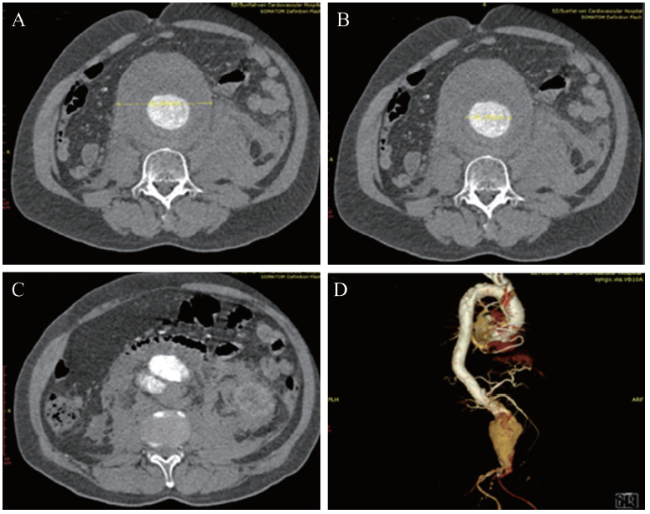

血常规示血红蛋白90 g/L,白细胞12.7 ×109/L,红细胞2.9×1012/L,血小板143×109/L。UCG示LVEF 0.55,心腔结构未见异常。全主动脉增强CT扫描提示腹主动脉瘤并腹主动脉破裂。术前CT血管三维重建显示患者肾下腹主动脉呈囊性扩张。瘤体最大直径约96 mm,瘤体真腔最大直径约45 mm,瘤体破口位于右侧肾动脉以下,瘤颈向右侧略偏斜,无明显扭曲,长度约15 mm,见图1

图1 一例腹主动脉瘤患者入院当日的CTA图像

A~C:轴位图像,D:VR容积成像显示侧位图像